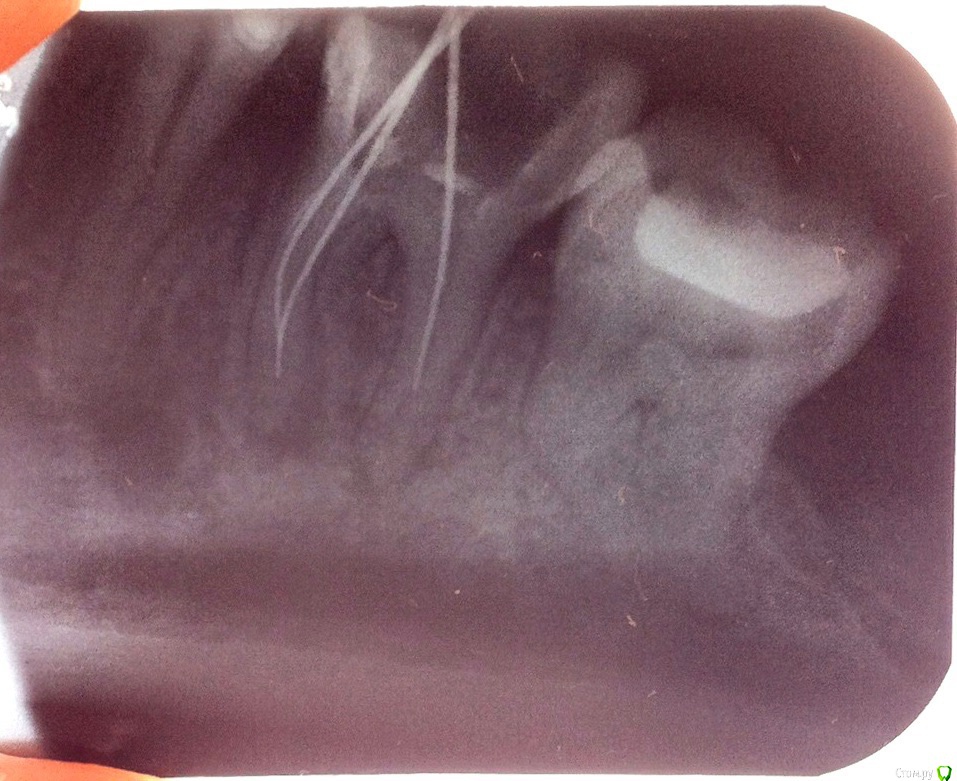

Ellie_58 Опубликовано 22 февраля, 2018 Поделиться Опубликовано 22 февраля, 2018 У меня был снимок после удаления 48 зуба, на котором увидели воспаление (кисту) 46 и сказали лечить (так он меня не беспокоил). В одной больнице два врача пытались пройти каналы, но не смогли. Первый сказал боится оставить инструмент, второй - все из-за предыдущего лечения-пломбировки (не особо понятная для меня причина). Третий врач в другой больнице выдала новый вариант, что каналы не доходят до конца корня, а разветвляются. Но всё-таки она попробовала и прошла один канал (судя по апекслокатору) и сказала, что лекарство кальций через него пройдет к кисте. Еще она сказала, что у меня есть небольшой обломок инструмента, но это нестрашно. В итоге она прекратила попытки пройти каналы с той же фразой, что не хочет оставлять инструменты в зубе. Снимок у меня только после попыток первого врача, но надеюсь на нем видно реально ли каналы разветвляются и их нельзя пройти? Поможет ли такое лечение? В каком случае удалять зуб? И после попыток зуб по разному то болит, то проходит - что это значит? Ссылка на комментарий